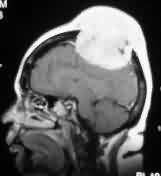

|

|

Convexity meningioma

with hyperostosis- MRI

|

Convexity meningioma

with hyperostosis- X-ray

|